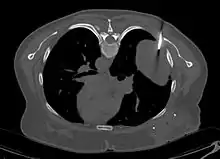

En tomodensitométrie[20],[31], quelle que soit la localisation, une tumeur fibreuse solitaire apparaît comme une masse tissulaire ovoïde ou lobulée, bien délimitée, refoulant les structures voisines sans les envahir. Elle se rehausse fortement après injection de produit de contraste. Les tumeurs de petite taille sont homogènes, mais les plus volumineuses présentent des plages hétérogènes de nécrose et d'hémorragie intra-tumorale. Il n'y a pas habituellement de calcifications et, lorsqu'elles sont présentes, elles sont de petite taille[31]. Les tumeurs malignes peuvent se présenter accompagnées de nodules pulmonaires métastatiques, et tendent à être plus volumineuses et plus hétérogènes[42].